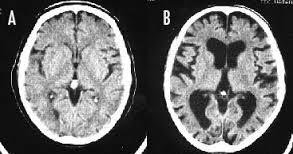

>>564 喫煙をすると、頭が悪くなるのは本当です。 長期の喫煙により、大脳皮質が薄くなり、認知機能が低下してしまうのです。 画像左(A)は正常な脳、右(B)は喫煙者の脳です。 正常な脳と比べて、喫煙者の脳は、萎縮して隙間だらけになってしまっています。 喫煙をやめても、元の状態に回復するまで、数十年はかかるそうです。